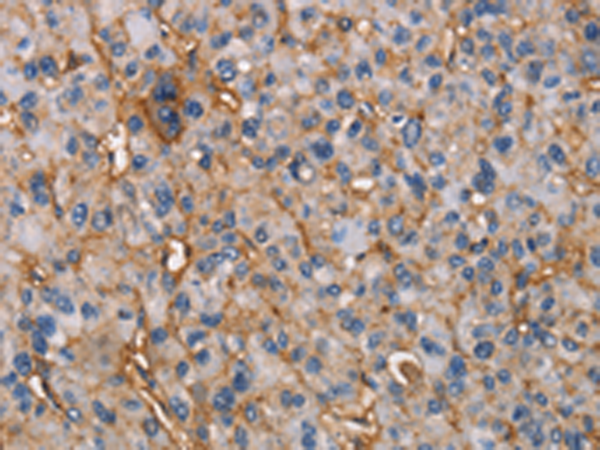

分类: 科研抗体货号: P07972别名: SHIK; SgK495应用: IHC反应种属: Human, Mouse, Rat